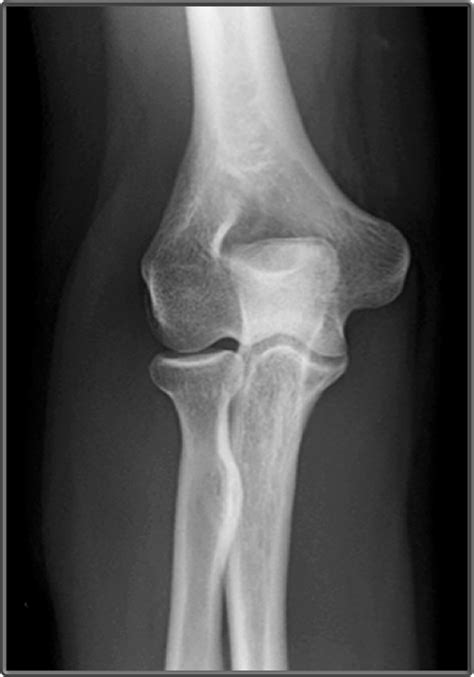

Now, let’s get to the juicy part: what do the images actually reveal? The AP view shows a two-dimensional picture of your elbow. Here’s what you can see and what doctors look for:

• Bones : The AP view clearly shows the bones of the elbow joint: the humerus (upper arm bone), the radius and ulna (forearm bones). Doctors examine these bones for fractures, dislocations, or any other abnormalities.

• Joint Space : The space between the bones in the joint (the joint space) is visible. Narrowing of this space can indicate arthritis.

• Alignment : The AP view allows doctors to assess the alignment of the bones. Proper alignment is essential for normal elbow function.

• Soft Tissues : Although not as detailed as other imaging methods like MRI, the AP view can sometimes show soft tissue changes, such as swelling or the presence of foreign objects.

• Fractures : The most obvious thing to look for is fractures, which appear as breaks or cracks in the bones. The radiologist will carefully examine the bones for any signs of these fractures.

• Bone Spurs : Doctors can see the bone spurs that can develop due to arthritis or other conditions.

Interpreting an AP elbow X-ray requires expertise. Radiologists are trained to identify subtle changes and abnormalities that might not be obvious to the untrained eye. They will use their knowledge and experience to provide a detailed report to your doctor, which will then guide your treatment. If you have any medical condition, the AP view will help the doctors to get a better diagnosis.